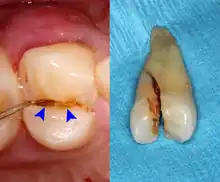

Dental trauma and cracked tooth syndrome

Cracked tooth syndrome refers to a highly variable[30] set of pain-sensitivity symptoms that may accompany a tooth fracture, usually sporadic, sharp pain that occurs during biting or with release of biting pressure,[31] or relieved by releasing pressure on the tooth.[10]: 24 The term is falling into disfavor and has given way to the more generalized description of fractures and cracks of the tooth, which allows for the wide variations in signs, symptoms, and prognosis for traumatized teeth. A fracture of a tooth can involve the enamel, dentin, and/or pulp, and can be orientated horizontally or vertically.[10]: 24–25 Fractured or cracked teeth can cause pain via several mechanisms, including dentin hypersensitivity, pulpitis (reversible or irreversible), or periodontal pain. Accordingly, there is no single test or combination of symptoms that accurately diagnose a fracture or crack, although when pain can be stimulated by causing separation of the cusps of the tooth, it's highly suggestive of the disorder.[10]: 27–31 Vertical fractures can be very difficult to identify because the crack can rarely be probed[10]: 27 or seen on radiographs, as the fracture runs in the plane of conventional films (similar to how the split between two adjacent panes of glass is invisible when facing them).[10]: 28–9

The prognosis for a cracked tooth varies with the extent of the fracture. Those cracks that are irritating the pulp but do not extend through the pulp chamber can be amenable to stabilizing dental restorations such as a crown or composite resin. Should the fracture extend though the pulp chamber and into the root, the prognosis of the tooth is hopeless.[10]: 25